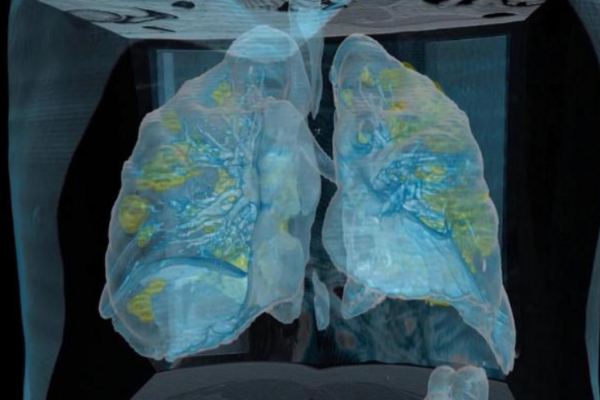

В сети показали легкие 59-летнего мужчины, больного коронавирусной инфекцией COVID-19.

Видео в формате 3D опубликовала университетская клиника Джорджа Вашингтона (чтобы посмотреть видео, доскролльте новость до конца).

Легкие пациента засняли через несколько дней после того, как у него появились первые симптомы. На кадрах видно большие повреждения и воспаления, выделенные желтым цветом. В легких здорового человека желтых участков не бывает.

Как пишет CNN, пациент нуждается в искусственной вентиляции легких, отдельный аппарат занимается циркуляцией его крови и насыщение ее кислородом.

«Это не 70 или 80-летний пациент с иммунодефицитом и диабетом. Кроме высокого кровяного давления, у него нет других серьезных медицинских проблем», – рассказал начальник грудной хирургии в больнице университета Джорджа Вашингтона Кот Мортман.

Он обратил внимание, что при таком повреждении легких заживление может продолжаться долго. Примерно 2-4% пациентов с COVID-19 получают необратимые повреждения.

«Я хочу, чтобы все увидели это и поняли, что может произойти», – сказал Мортман и добавил, что «люди должны отнестись к этому серьезно».